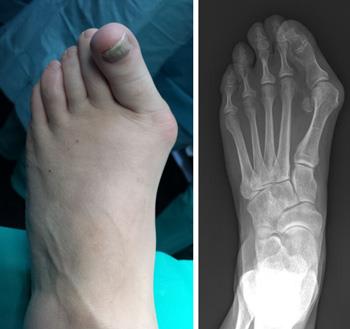

Nonsurgical treatments that may relieve the pain and pressure of a bunion include. Bunionectomy and osteotomy may be performed under local general or spinal anesthesia on an outpatient basis in a hospital surgical center or doctors office usually by an orthopedic podiatric or other specialist foot surgeon. Cutting and repositioning the bones is called an osteotomy.

Treatment may include joint mobilisation and alignment techniques massage muscle and joint stretches taping a bunion splint or orthotic. The main operation for bunions is an osteotomy. Your doctor might recommend a prescription or over-the.

Visit your bunion specialist to get fitted for a custom orthotic insert. Cutting or scraping away the bunion.